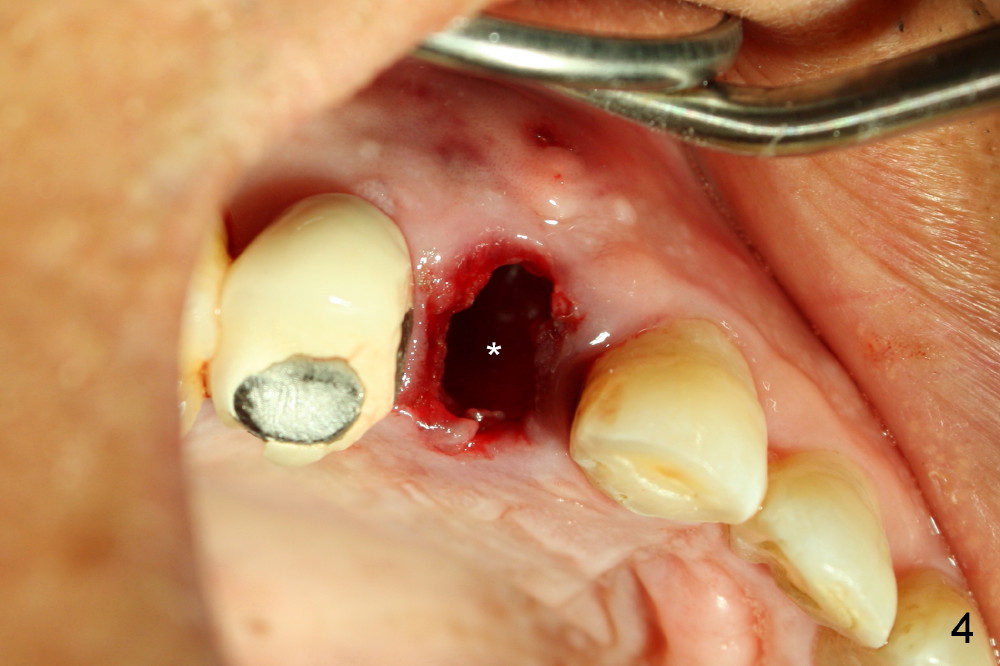

A 57-year-old man refuses treatment for the tooth #5 for 22 months (Fig.1). He suddenly shows up because of severe bleeding from the fistula of the tooth (Fig.2 <). After lengthened discussion, he agrees extraction (Fig.4) and immediate implant (Fig.5-8).

Eighteen days postop, the patient returns for #4 root canal therapy; PA shows bone graft next to the implant (Fig.11 *). Twenty-two days postop, the immediate provisional is dislodged with loss of bone graft over the middle of the buccal surface of the implant (Fig.12 *). The implant and abutment are prepared so that the margin is advanced apically (Fig.13 ^) with accentuation of the retention grooves (*). The provisional is relined and recemented.